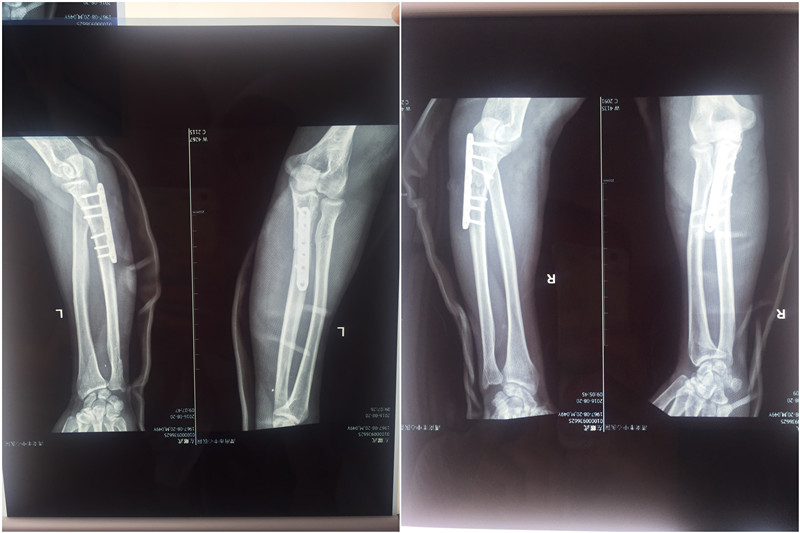

手术前

手术后